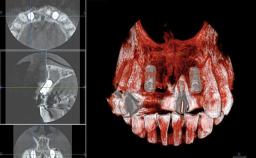

Replacement of Four Incisors with a Fixed Partial Denture on Two Narrow-Neck Implants after Implant Failure

| Type of Implants | One-Piece|Reduced-Diameter |

| Bone Augmentation | Horizontal|Staged|Vertical |

| Augmentation Materials | Autogenous block(s)|Xenogenous|Membrane |

| Bone Volume | Deficient vertically or deficient vertically AND horizontally |